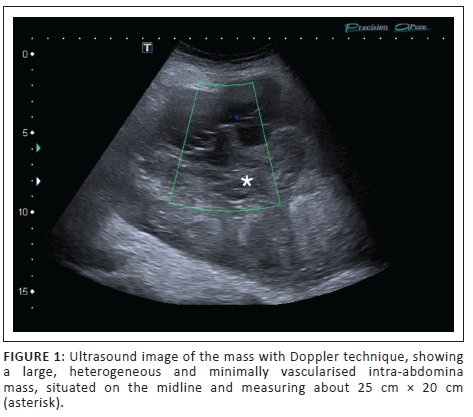

An 80-year-old female patient was referred by her general practitioner and presented at the radiology department for an abdominal ultrasound. She complained about painless abdominal swelling for several weeks. A firm intra-abdominal mass was palpable during clinical examination. The abdominal ultrasound showed a large, heterogeneous and minimally vascularised intra-abdominal midline mass, measuring about 25 cm × 20 cm (Figure 1).